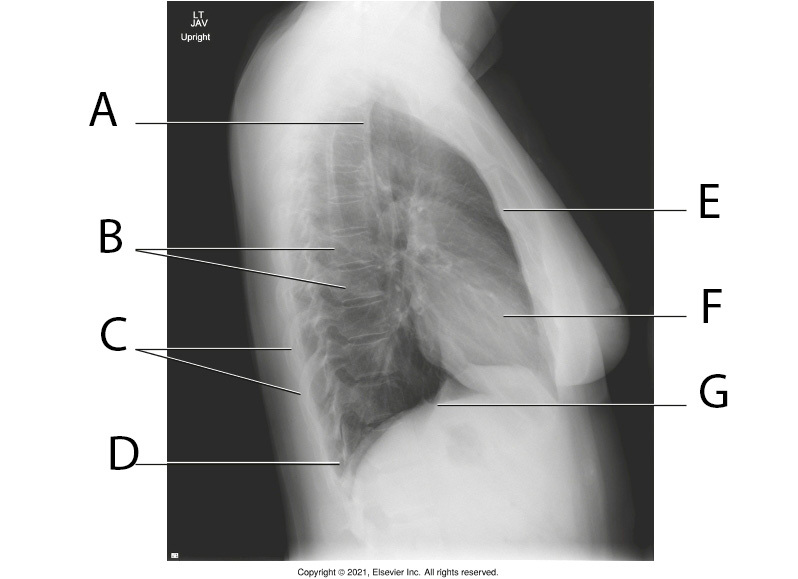

10

Q

A

Apicies

11

B

Thoracic Vertabrae

12

C

Posterior Ribs

13

D

Costrophrenic Angle

14

E

Body of Sternum

15

F

Heart

16

G